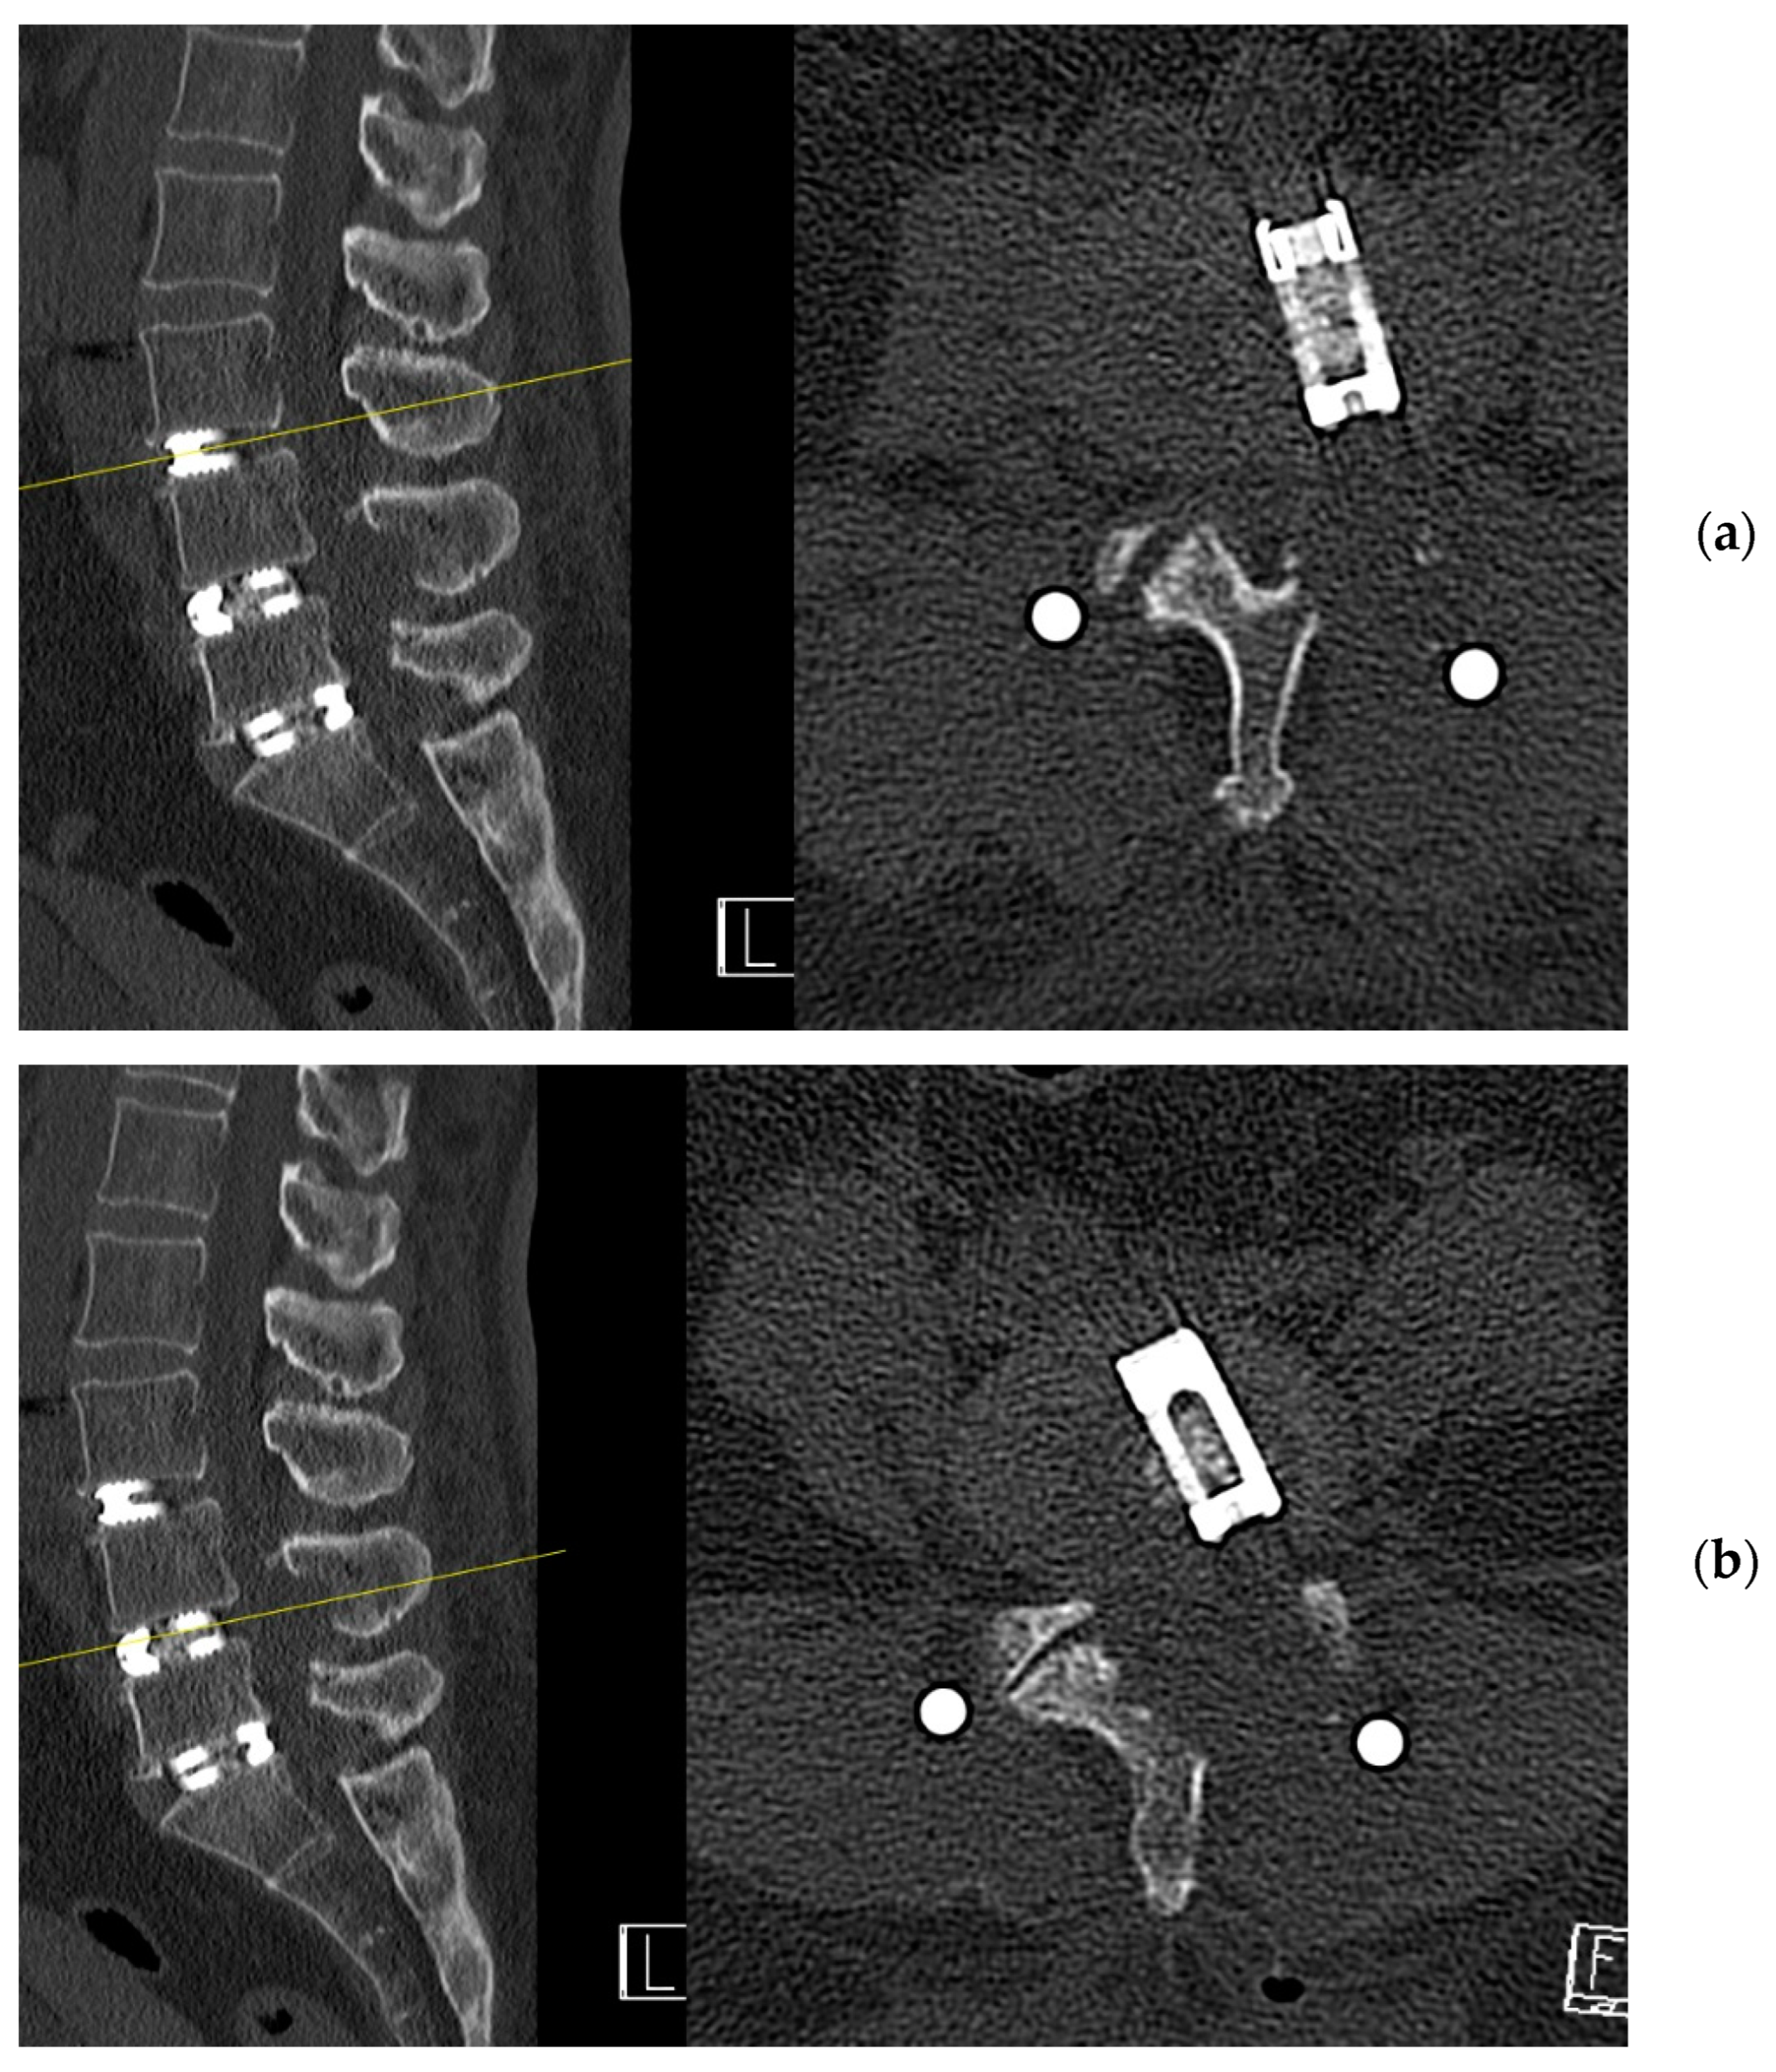

4. Case Example

4.1. Case 1: Madam M

4.2. Case 2: Madam R

4.3. Case 3: Madam M